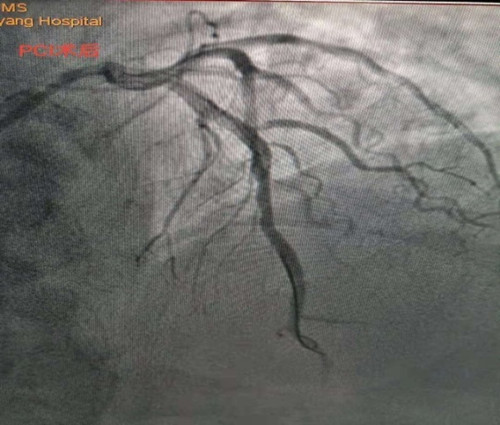

李新國主任為蒿大叔做了急診冠脈造影檢查,提示前降支近中段90%狹窄, D1開口99%狹窄,可見血栓影,結合術前心臟超聲檢查發現患者心臟腱索水平以下左室前間壁、前壁、前側壁運動搏幅減低,梗死范圍大,考慮罪犯血管為前降支近中段,在前降支近中段植入了一枚支架,開通閉塞血管。經過1個多小時的搶救,蒿大叔總算從鬼門關被救了回來了。